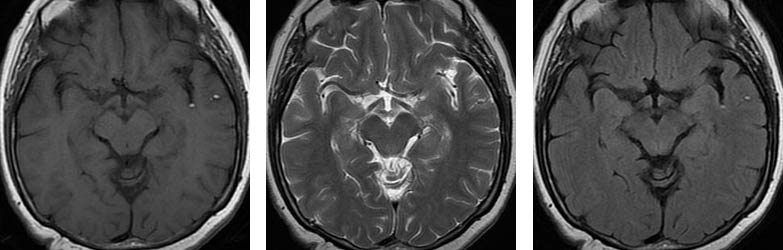

Üç farklı seviyeden aksiyal planda TlAG, T2AG ve FLAIR görüntüler Subaraknoid mesafelerde, özellikle BOS'un hipointens izlendiği TlAG ve FLAIR sekanslarda dağınık milimetrik hiperintens od aklar dikkati çekmektedir.

Pantopaque yağa benzer şekilde kısa T1 ve T2 reIaksasyon sürelerine sahiptir. Bu nedenle Tl ve T2AG'Ierde hiperintens olarak izIenirIer ve özellikle BOS mesafelerinin baskılandığı T1AG ve FLAIR sekanslarında dikkati çekerler.